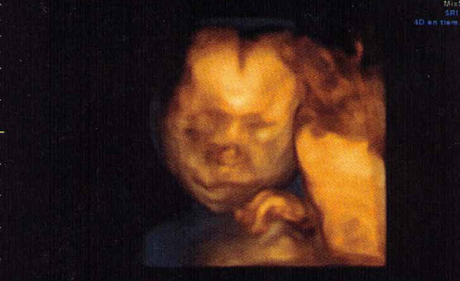

A estas alturas del embarazo, también me doy cuenta que en cuestión de 3 meses, seré responsable de otro pequeño ser a mi cargo, será otra experiencia completamente diferente, otra etapa a la que me enfrentaré.Solo espero que todo vaya bien, el resto irá surgiendo. Tengo ya ganas de ver su carita, me pregunto...sacará las orejas de soplillo de mi hermano?, será tan buena como mi pequeña? será tan guapo y listo como el padre? tan gracioso y simpático como la mami? romperá la tranquilidad que reina en casa con nosotros tres? jajajaja ayyyyy qué fácil es hacer niños....Solo espero poder entregarme con él como lo hice y hago con mi pequeña, para sentir que lo hago bien y que lo hago feliz...